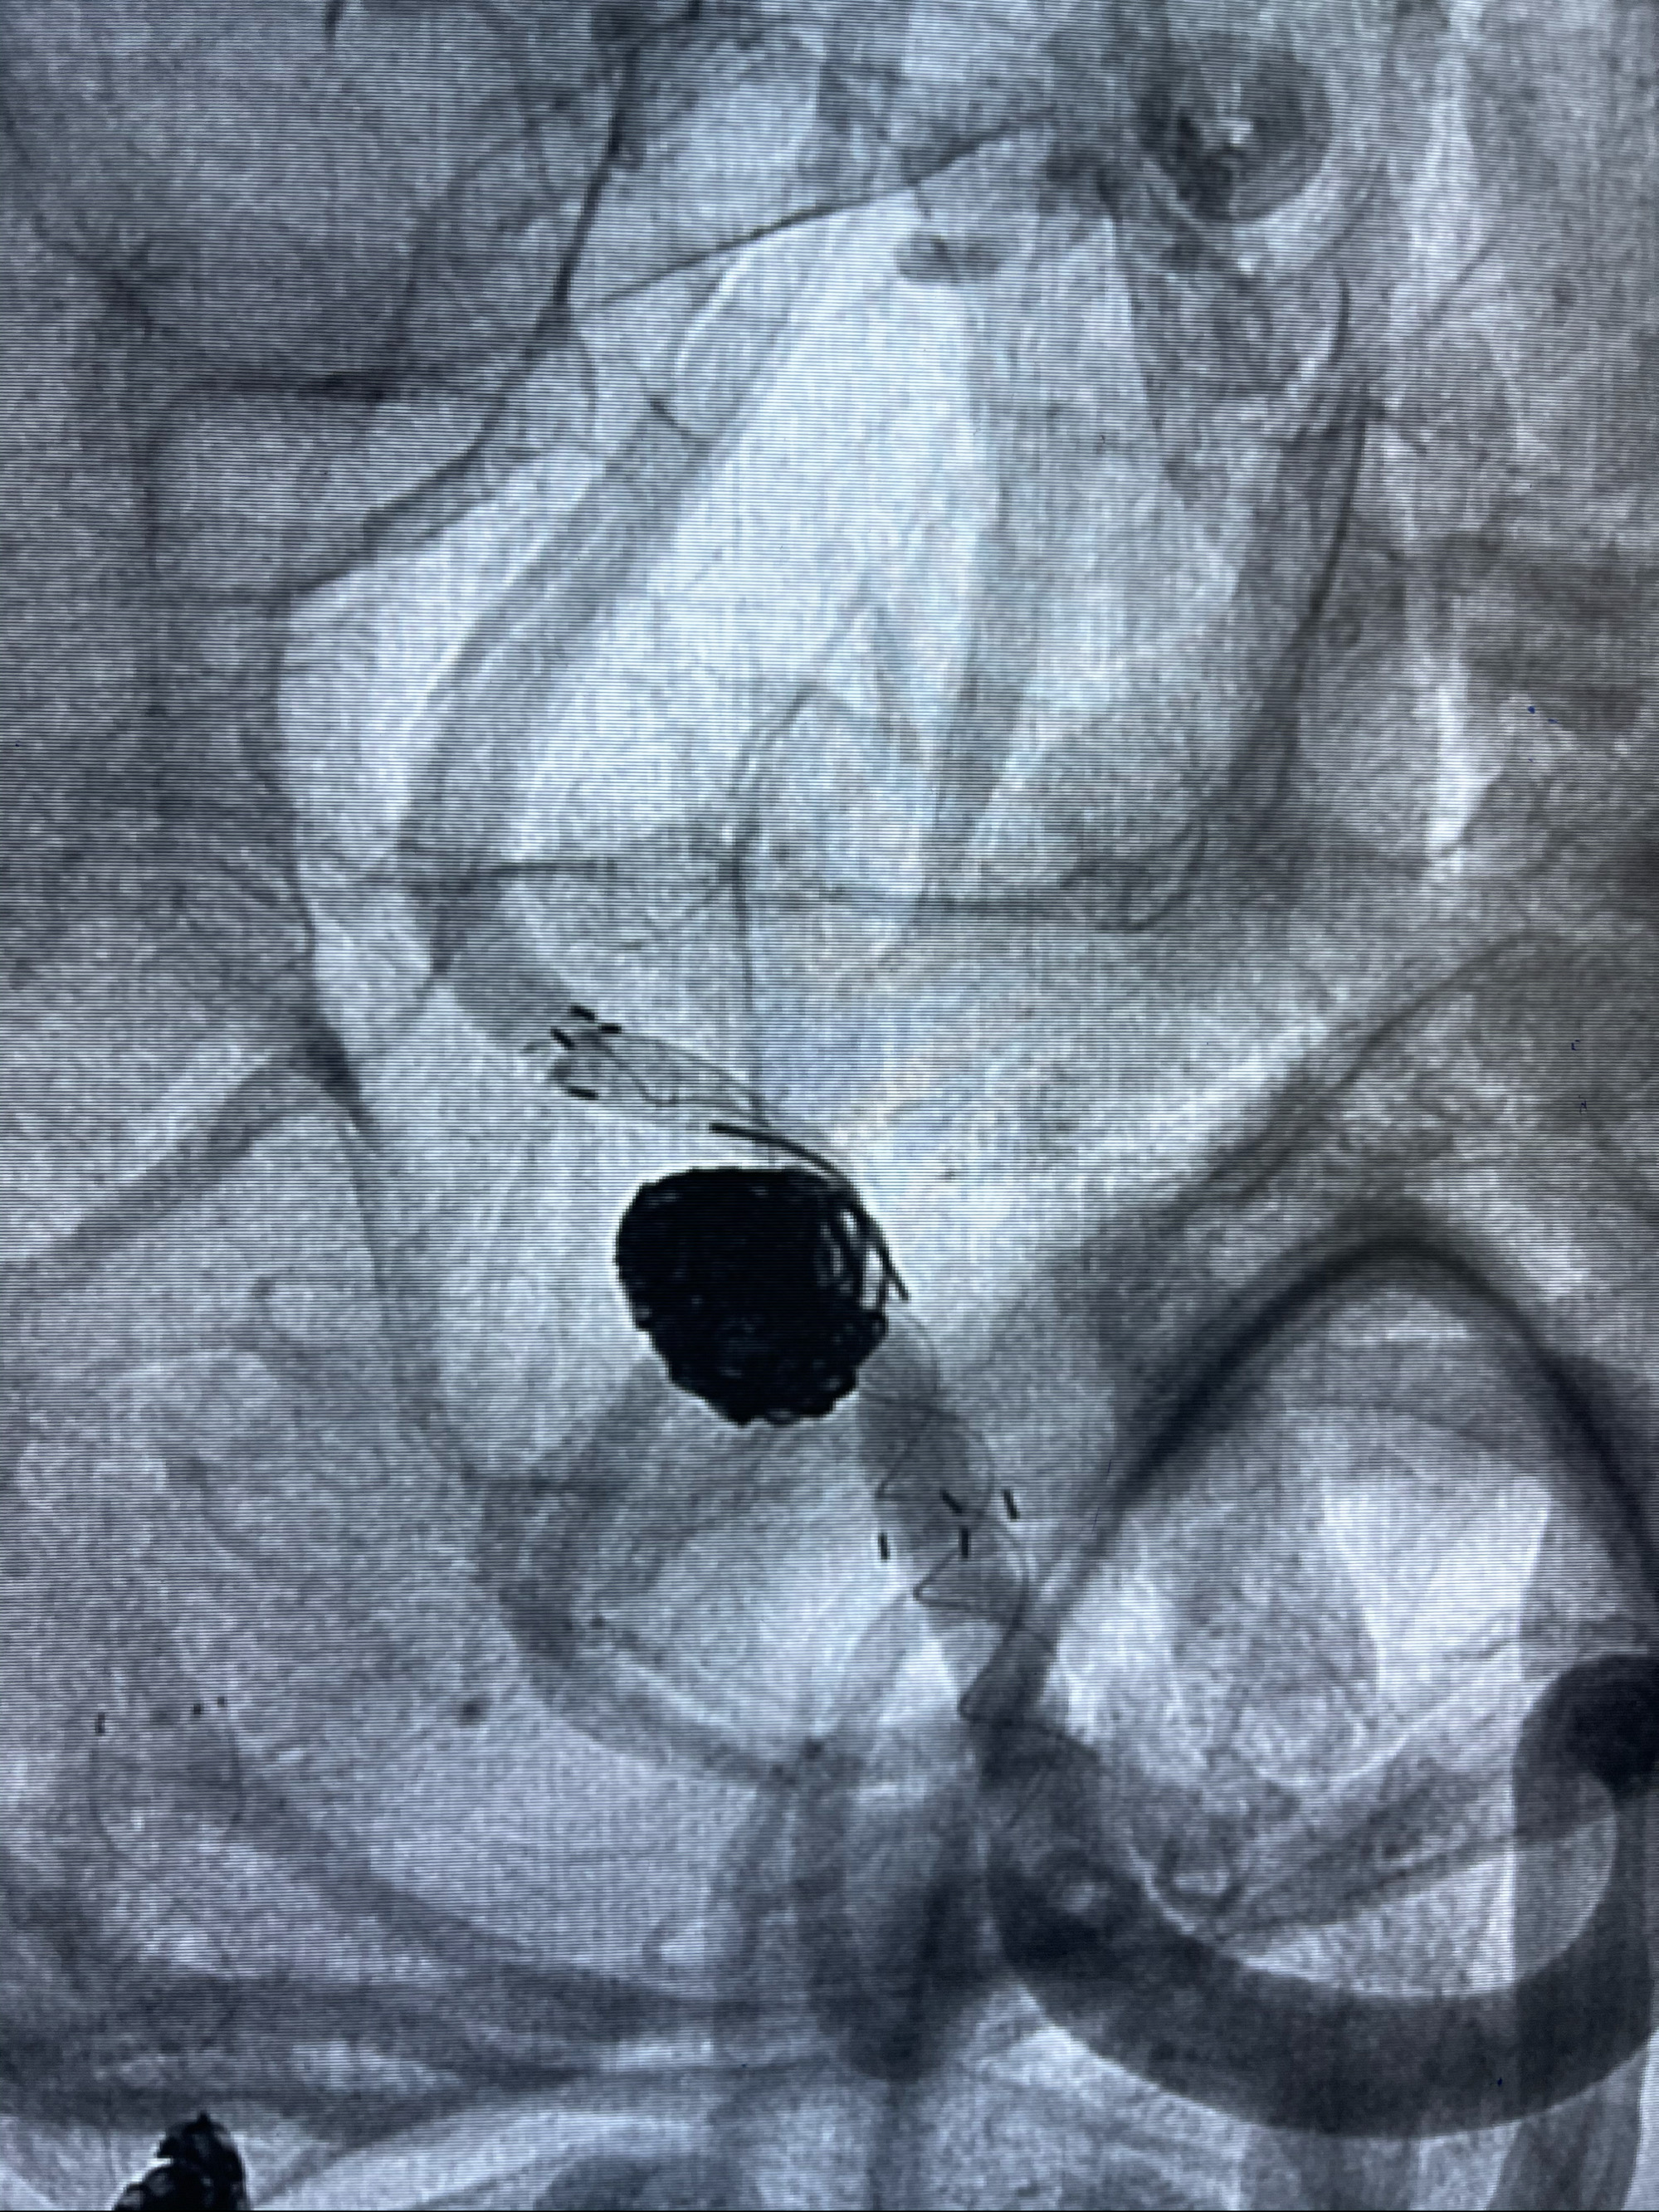

1.Enterprise4.0-23mm;

2.Tubridge3.5-30mm密网支架

支架到位

支架释放,透视下